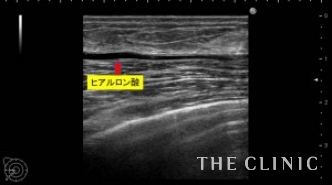

昨年12月にヒアルロン酸豊胸の手術を受けたが、2ヶ月前からしこりが気になり始めたため手術を受けたクリニックに相談に行くと、しこり除去後2~3ヶ月経たないと脂肪注入は出来ないと言われたそうです。患者様はそんなに待てないとのことでヒアルロン酸除去とCRF豊胸のご相談で当院にいらっしゃいました。エコーで確認すると、乳腺と大胸筋の間にヒアルロン酸がたくさん残っており、一部カプセルを形成してしこりになっていました。CRF豊胸を行う前にヒアルロン酸を溶解除去しないと、コンデンスリッチファットの定着が下がる可能性があるため、エコー下に確実に吸引除去する必要があります。ヒアルロン酸が少量であれば、ヒアルロン酸除去と同時にCRF豊胸が可能ですが、この方は大量にヒアルロン酸が残っていたため、まずはヒアルロン酸除去を行いました。

16ゲージの注射針を確実にヒアルロン酸のしこりに入れて、ヒアルロニダーゼ(ヒアルロン酸溶解剤)を注入し、溶けたヒアルロン酸は吸引除去します。

両側合わせて150㏄のヒアルロン酸を吸引除去しました。

ヒアルロン酸注入によるしこりのエコー診断カルテ